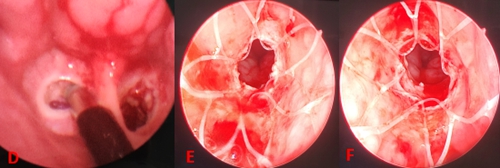

手術(shù)如期進(jìn)行,治療團(tuán)隊(duì)在鼻內(nèi)鏡輔助下經(jīng)口利用低溫等離子刀一點(diǎn)點(diǎn)消融、打通左側(cè)后鼻孔閉鎖板,隨后在雙側(cè)后鼻孔處放置全降解鼻竇藥物支架,以防鼻孔被再次堵住。術(shù)后,芳芳來院進(jìn)行定期復(fù)查,恢復(fù)良好,鼻塞、流涕、打鼾、張口呼吸等情況均完全消失。

圖D:術(shù)中在鼻內(nèi)鏡輔助下經(jīng)口利用低溫等離子刀消融左側(cè)后鼻孔閉鎖板

圖E、F:術(shù)中于雙側(cè)后鼻孔處放置全降解鼻竇藥物支架